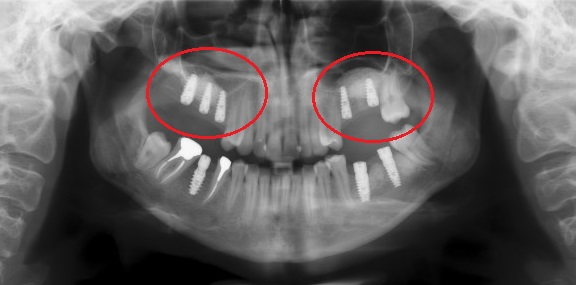

На рентгене виден недостаток альвеолярного гребня, показан синус-лифтинг. Фото с сайта https://akademstom.ru/implantatsiya-verhney-chelyusti/

Чем дольше отсутствуют зубы, которые находятся под гайморовыми пазухами, тем меньше жевательной нагрузки получает верхняя челюсть. И без того рыхлая верхняя челюстная кость быстро атрофируется, уменьшается в объеме.

Длина стандартного импланта – 8-20 мм. Если высота альвеолярного гребня меньше, то имплант может пройти насквозь, повредить пазуху и вызвать осложнения.

КТ позволяет с точностью до доли миллиметра определить высоту и ширину альвеолярного гребня, размер и расположение гайморовых пазух. На основе полученных данных врач подбирает длину импланта, место и наклон установки.

Применяется, если альвеолярный гребень тоньше, чем нужно. Дно гайморовой пазухи приподнимается, образованное пространство заполняется костным материалом – увеличивается объем альвеолярного гребня. Исключается риск выхода импланта за пределы кости и перфорации дна гайморовой пазухи.